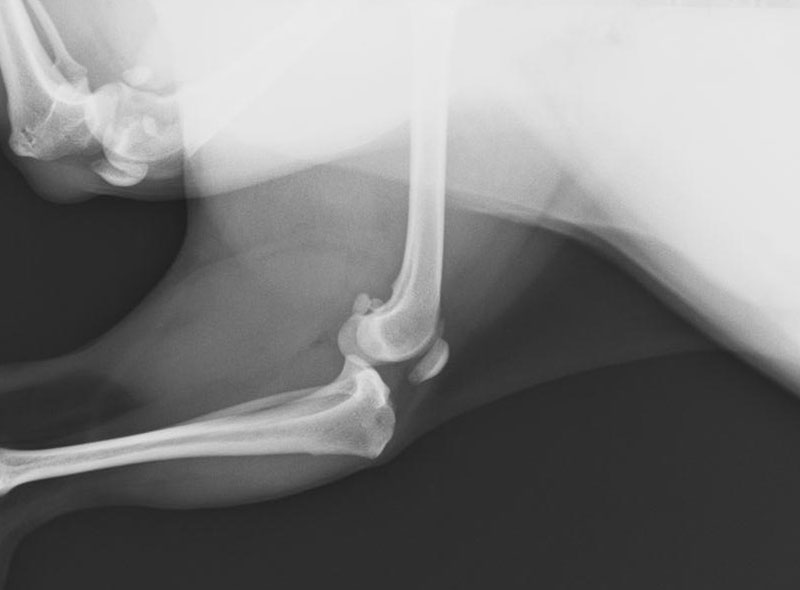

前十字靭帯断裂

前十字靭帯は、大腿骨と下腿骨(脛骨)が前後にずれない様につなぎ止めている靭帯です。

この靭帯が、激しい運動や踏み外しなどにより、ちぎれてしまうと、足を上げっぱなし、または上げ気味に使います。

完全断裂の場合は、靭帯を再建する手術が必要となります。

-

前十字靭帯完全断裂 手術前

前十字靭帯完全断裂 手術後